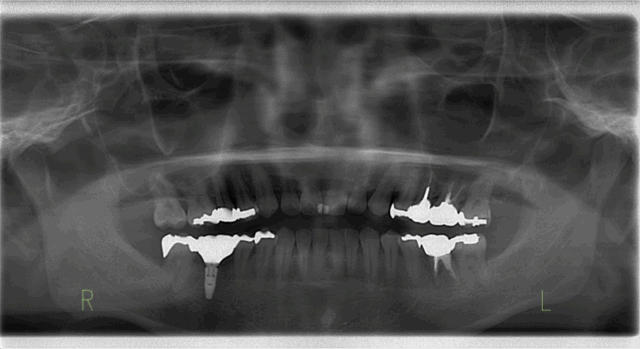

Before

After

| 通院時の年齢 | 55歳 |

|---|---|

| 性別 | 女性 |

| 通院回数 | 約1年 |

| 通院目的 | 見た目をきれいにしたい |

| 処置内容 | 下顎臼歯部欠損→インプラント 下顎前歯部根尖性歯周炎→根管治療 既存の上下補綴物(セラミック冠)を撤去し、咬合(かみ合わせ)の再建や人口歯の形態の変更などのフルマウス治療 |

| 備考 | 【診断名】下顎臼歯部(奥歯)欠損、下顎前歯根尖性歯周炎 下顎前歯の根尖性歯周炎により病巣から膿が出ていたが、マイクロスコープを用いた根管治療を行うことにより、下顎前歯を残すことが可能となった。 |